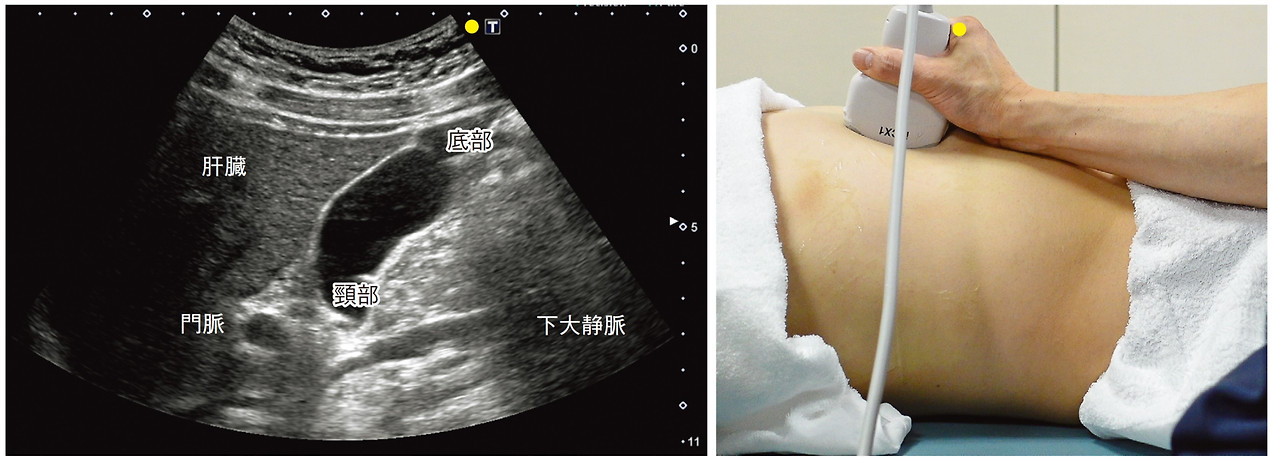

- 검사 위치: 검사 중에는 보통 누운 자세로 진행합니다. 검사자는 복부에 젤을 바르고, 초음파 기계를 사용하여 복부를 스캔합니다.

- 이미지 촬영: 초음파 기계가 복부 내부의 이미지를 생성하고, 이를 모니터를 통해 실시간으로 확인합니다.